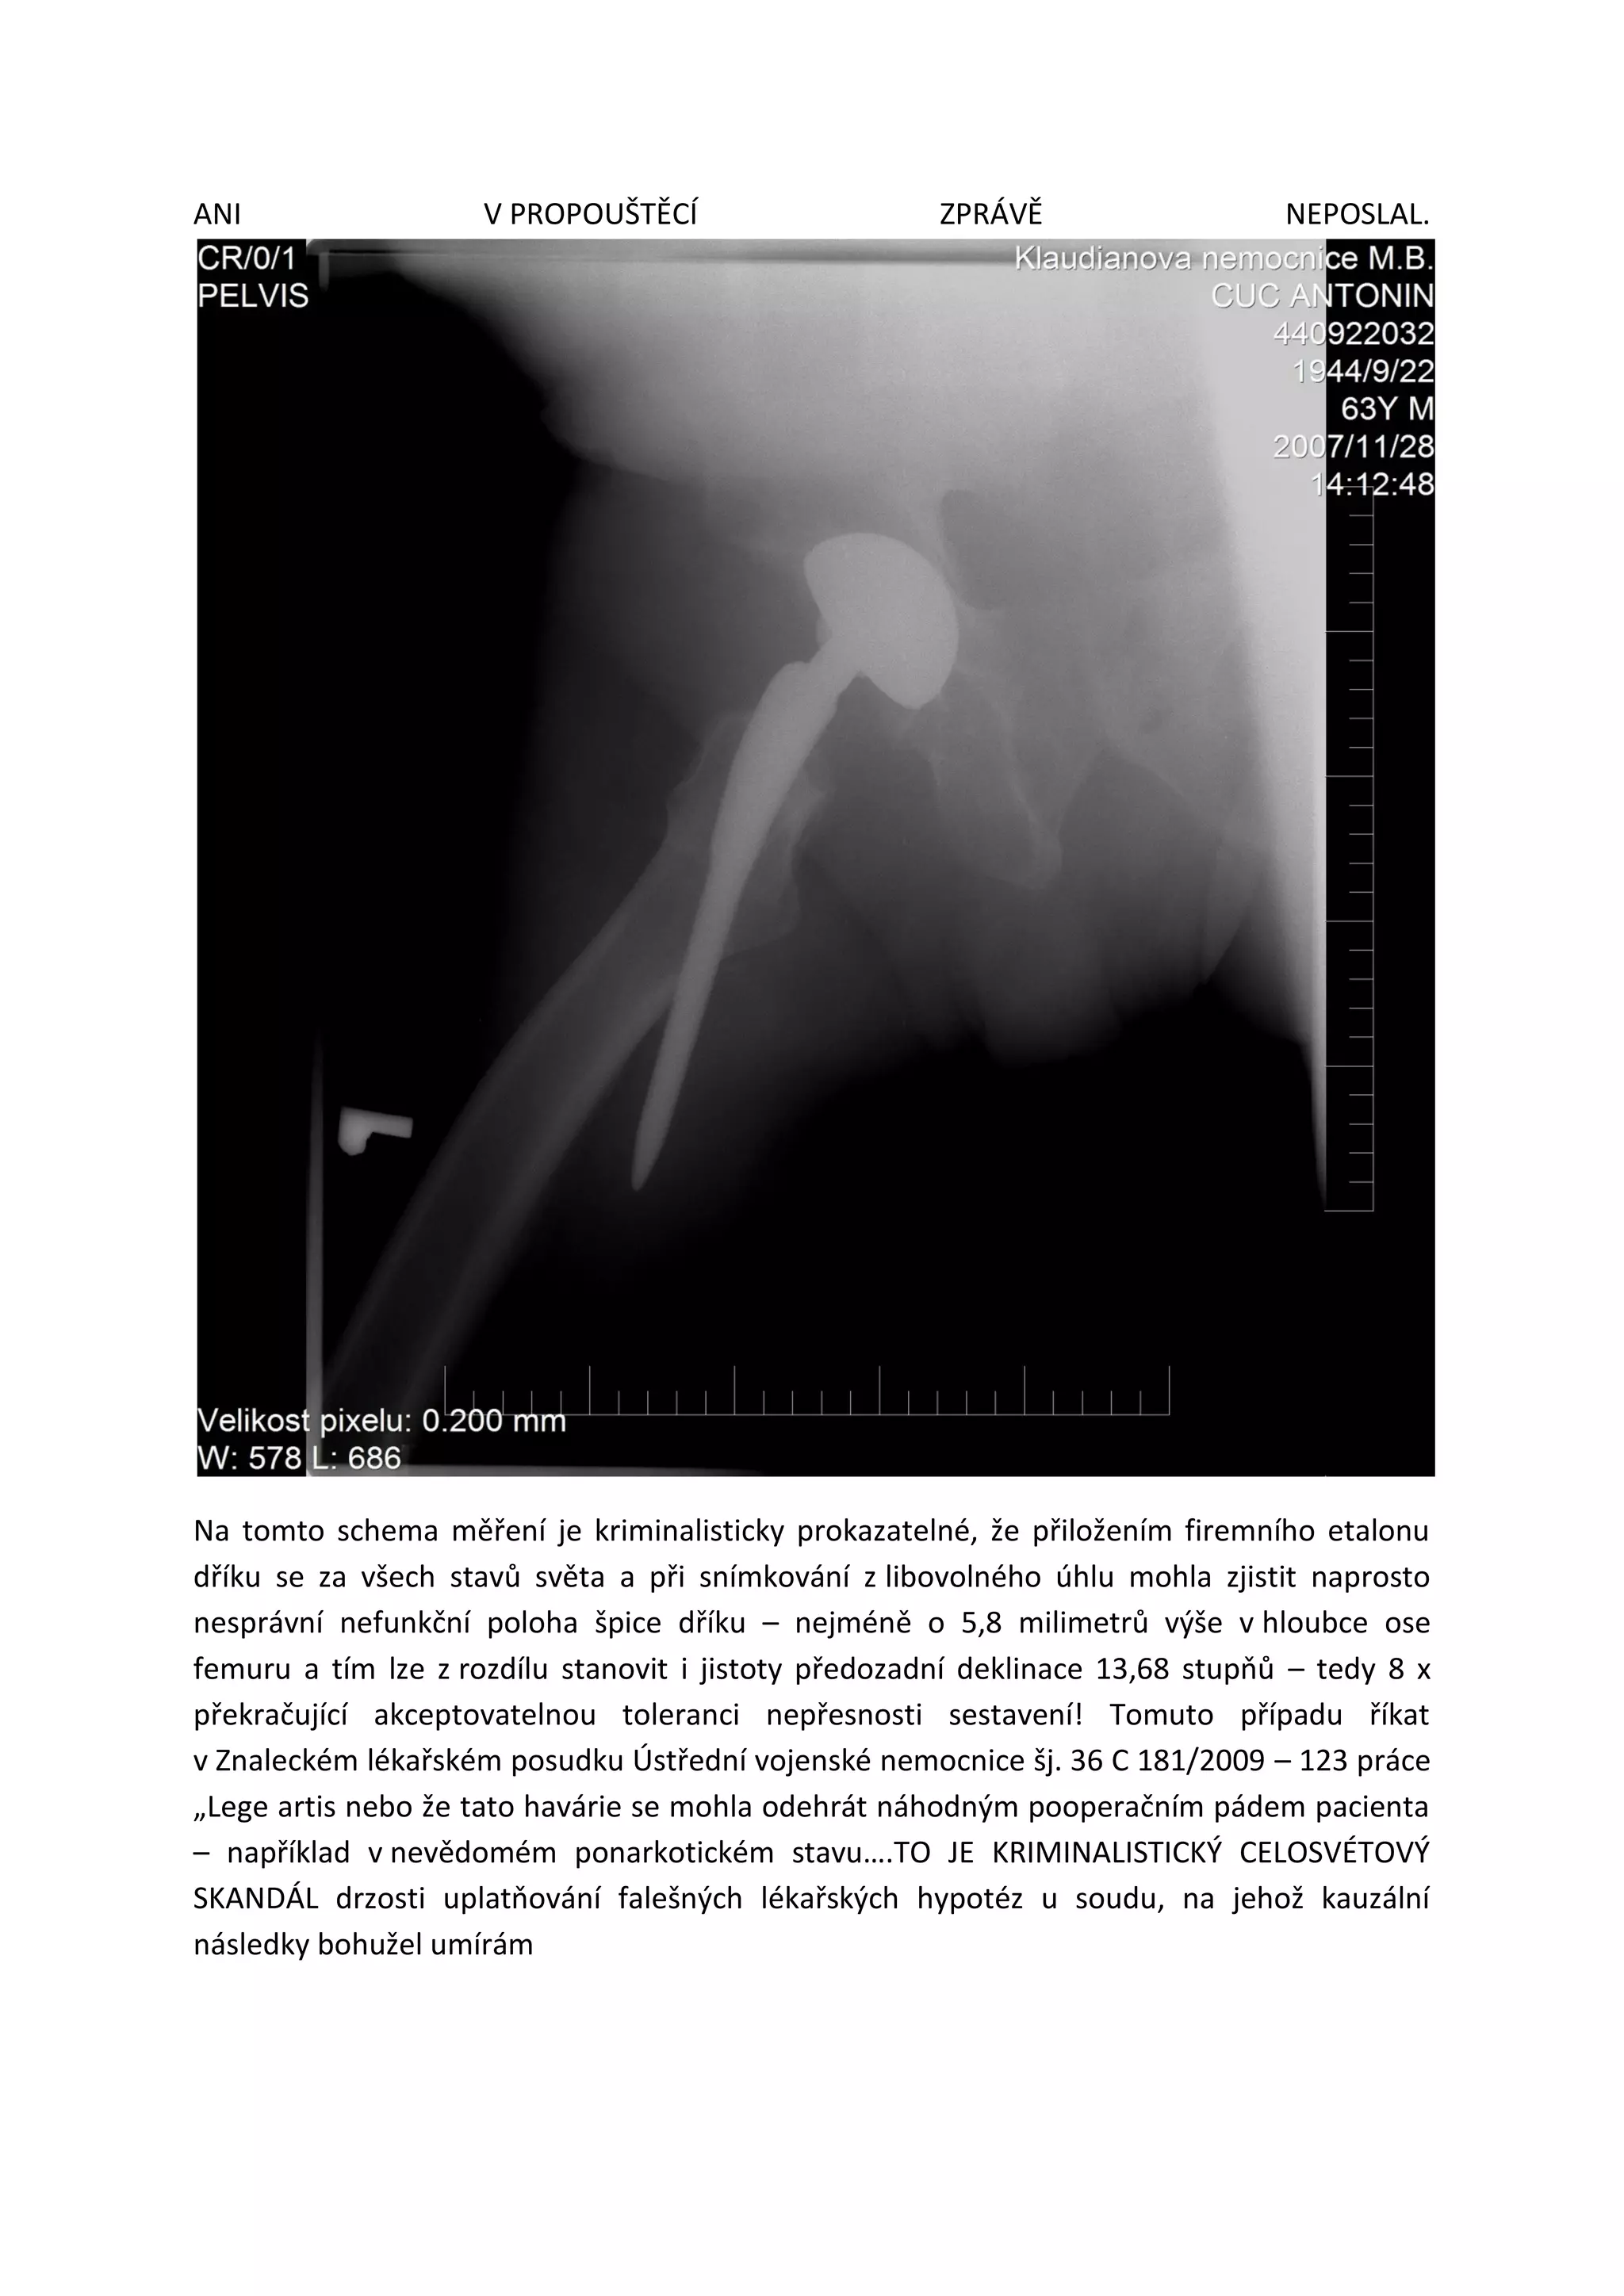

Také tento další RTG snímek havárie ze sálové situace vzniklé dne 13.11.2007 byl u žalované

Oblastní nemocnice Mladá Boleslav pořízen také teprve až dne 28.11.2007 a jasně sada

všech dostupných pooperačních snímků umožňuje v režimu Printu 3 D vytisknout havárii

trojrozměrně v konzistentním spojení elektronických dat firemního radiologického etalonu

užitého dříku a těchto 3 pooperačních snímků – s kriminalistickým závěrem: Havárie byla

způsobeny výhradně na sále 13.11.2007 a to prokazuje zcela vadnou nezákonnou instalací

dříku do osy femuru, kde neexistence nějakých viditelných dalších kostních zlomků

prokazuje, že ortoped MUDr. František Vurm nechtěně prorašploval falešnou díru v tvarově

připravovaném lůžku pro uložení proximální části femuru pro uložení komponenty dříku

touto falešnou díru, kterou při následném pokusu ortopedického narážení kladívkem dříku

zjevně špice dříku projela falešnou trajektorii zcela mimoosově vůči ose femuru a zůstala pak

vězet opřena v bocích konstrukčního úkosu dříku 1 : 100, zdánlivě pevně - hluboko

v svalovině stehna pacienta - naprosto v nefunkční poloze s vysoením 13,68 stupňů a tím

vzniklo jistě krvácení, krevní otok a tím vznikl fatální mnohadenní útisk nervu ischiadicu

s následkem trvalé úplné plegie, kterou bylo možno ovšem potenciálně s vysokou úspěšností

řešit ještě neurochirurgickou rekonstrukcí nervu ischiadicu do 4 měsíců od vzniku havarijního

polytrauma na sále 13.11.2007 – JENŽE PRIMÁŘ ORTOPEDIE PACIENTA NA NEUROCHIRURGII

ANI V PROPOUŠTĚCÍ ZPRÁVĚ NEPOSLAL.

Na tomto schema měření je kriminalisticky prokazatelné, že přiložením firemního etalonu

dříku se za všech stavů světa a při snímkování z libovolného úhlu mohla zjistit naprosto

nesprávní nefunkční poloha špice dříku – nejméně o 5,8 milimetrů výše v hloubce ose

femuru a tím lze z rozdílu stanovit i jistoty předozadní deklinace 13,68 stupňů – tedy 8 x

překračující akceptovatelnou toleranci nepřesnosti sestavení! Tomuto případu říkat

v Znaleckém lékařském posudku Ústřední vojenské nemocnice šj. 36 C 181/2009 – 123 práce

„Lege artis nebo že tato havárie se mohla odehrát náhodným pooperačním pádem pacienta

– například v nevědomém ponarkotickém stavu….TO JE KRIMINALISTICKÝ CELOSVÉTOVÝ

SKANDÁL drzosti uplatňování falešných lékařských hypotéz u soudu, na jehož kauzální

následky bohužel umírám